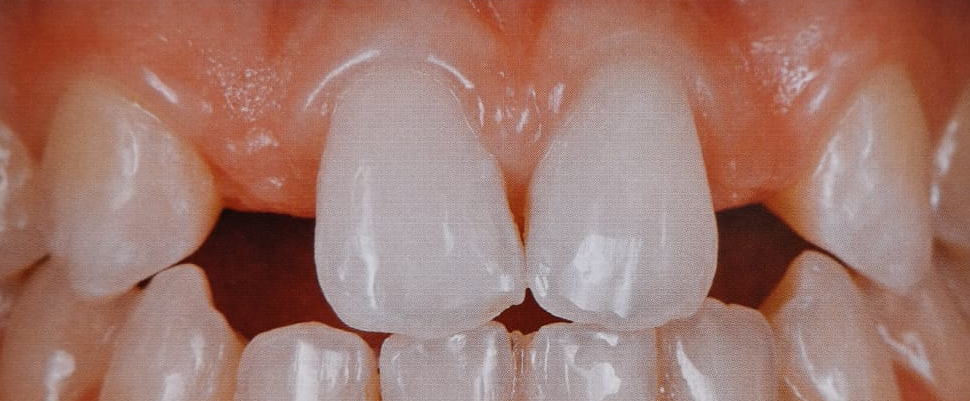

Veja aqui como são os novos critérios quantitativos que mudam a percepção da estética na prótese unitária sobre implantes.